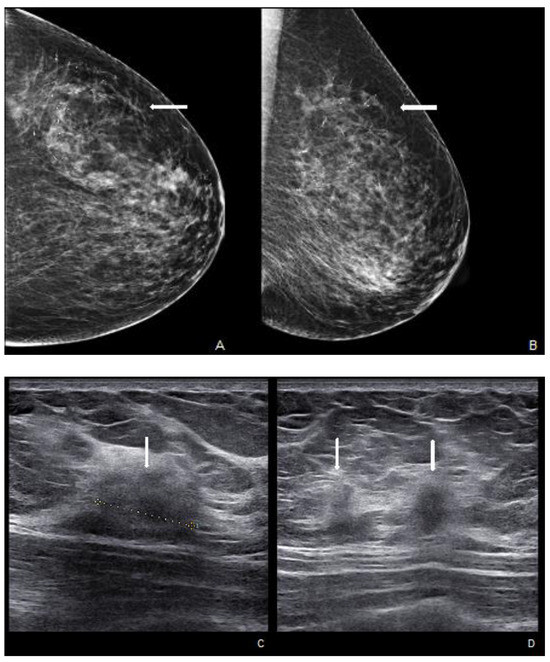

Figure 5.

Woman with pruritic erythema and serous discharge of the right nipple and history of ipsilateral nipple-sparing mastectomy (10 years prior). Exfoliative cytology was performed with PC positivity. In the US, superficial hypoechogenic retroareolar areas with ectasia ductal are observed.

US is a non-invasive, repeatable, and widely available technique. Its inclusion in the initial assessment could benefit and warrants consideration, mainly when DM yields negative results, especially in women with denser breast tissue. Similar to mammographic MPD findings, US alterations are nonspecific and include expected changes for BC treatments, including hypoechogenic masses, microcalcifications, ductal ectasia, NAC flattening, asymmetry, and thickening [26,47,48] (Figure 5). Additionally, US offers an option of immediate image-guided intervention and improves the diagnostic accuracy for axillary lymph node status. However, not all underlying BC can be identified through the US. MRI’s higher sensitivity in evaluating the retroareolar region provides crucial information for clinically evident MPD cases with occult findings in DM and US and for the preoperative assessment of disease extent in patients eligible for breast-conserving therapy [26,47]. In addition, thanks to contrast enhancement, it shows nipple involvement [49]. MRI findings include asymmetric and abnormal NAC enhancement patterns, sometimes associated with non-mass-like enhancement or suspicious masses elsewhere in the breast [26,47,50], even a distant site with no apparent anatomic connection, about possible MPD multifocality and multicentricity (Figure 6). MRI may also evaluate lymph node status, raising concerns about axillary or internal mammary involvement. However, it is essential to note that false-negative MRI results for NAC evaluation in MPD cases have also been reported [25,50], probably for less-aggressive disease forms. Therefore, all clinically suspicious findings must undergo biopsy, regardless of negative imaging results. A full-thickness NAC biopsy with histological and immunohistochemical evaluation is the gold standard for establishing an ultimate diagnosis [38]. Research examining the molecular markers in MPD cases has revealed an expression of HER-2/neu, cytokeratin 7 (CK7), mucin 1 (MUC1), and human milk fat globule, and positive staining with CAM 5.2 antibody [51,52]. Exfoliative cytology with PC demonstration may be helpful, but a negative result can occur; its use has been postulated as an easy screening test for eczematous skin changes to the nipple.